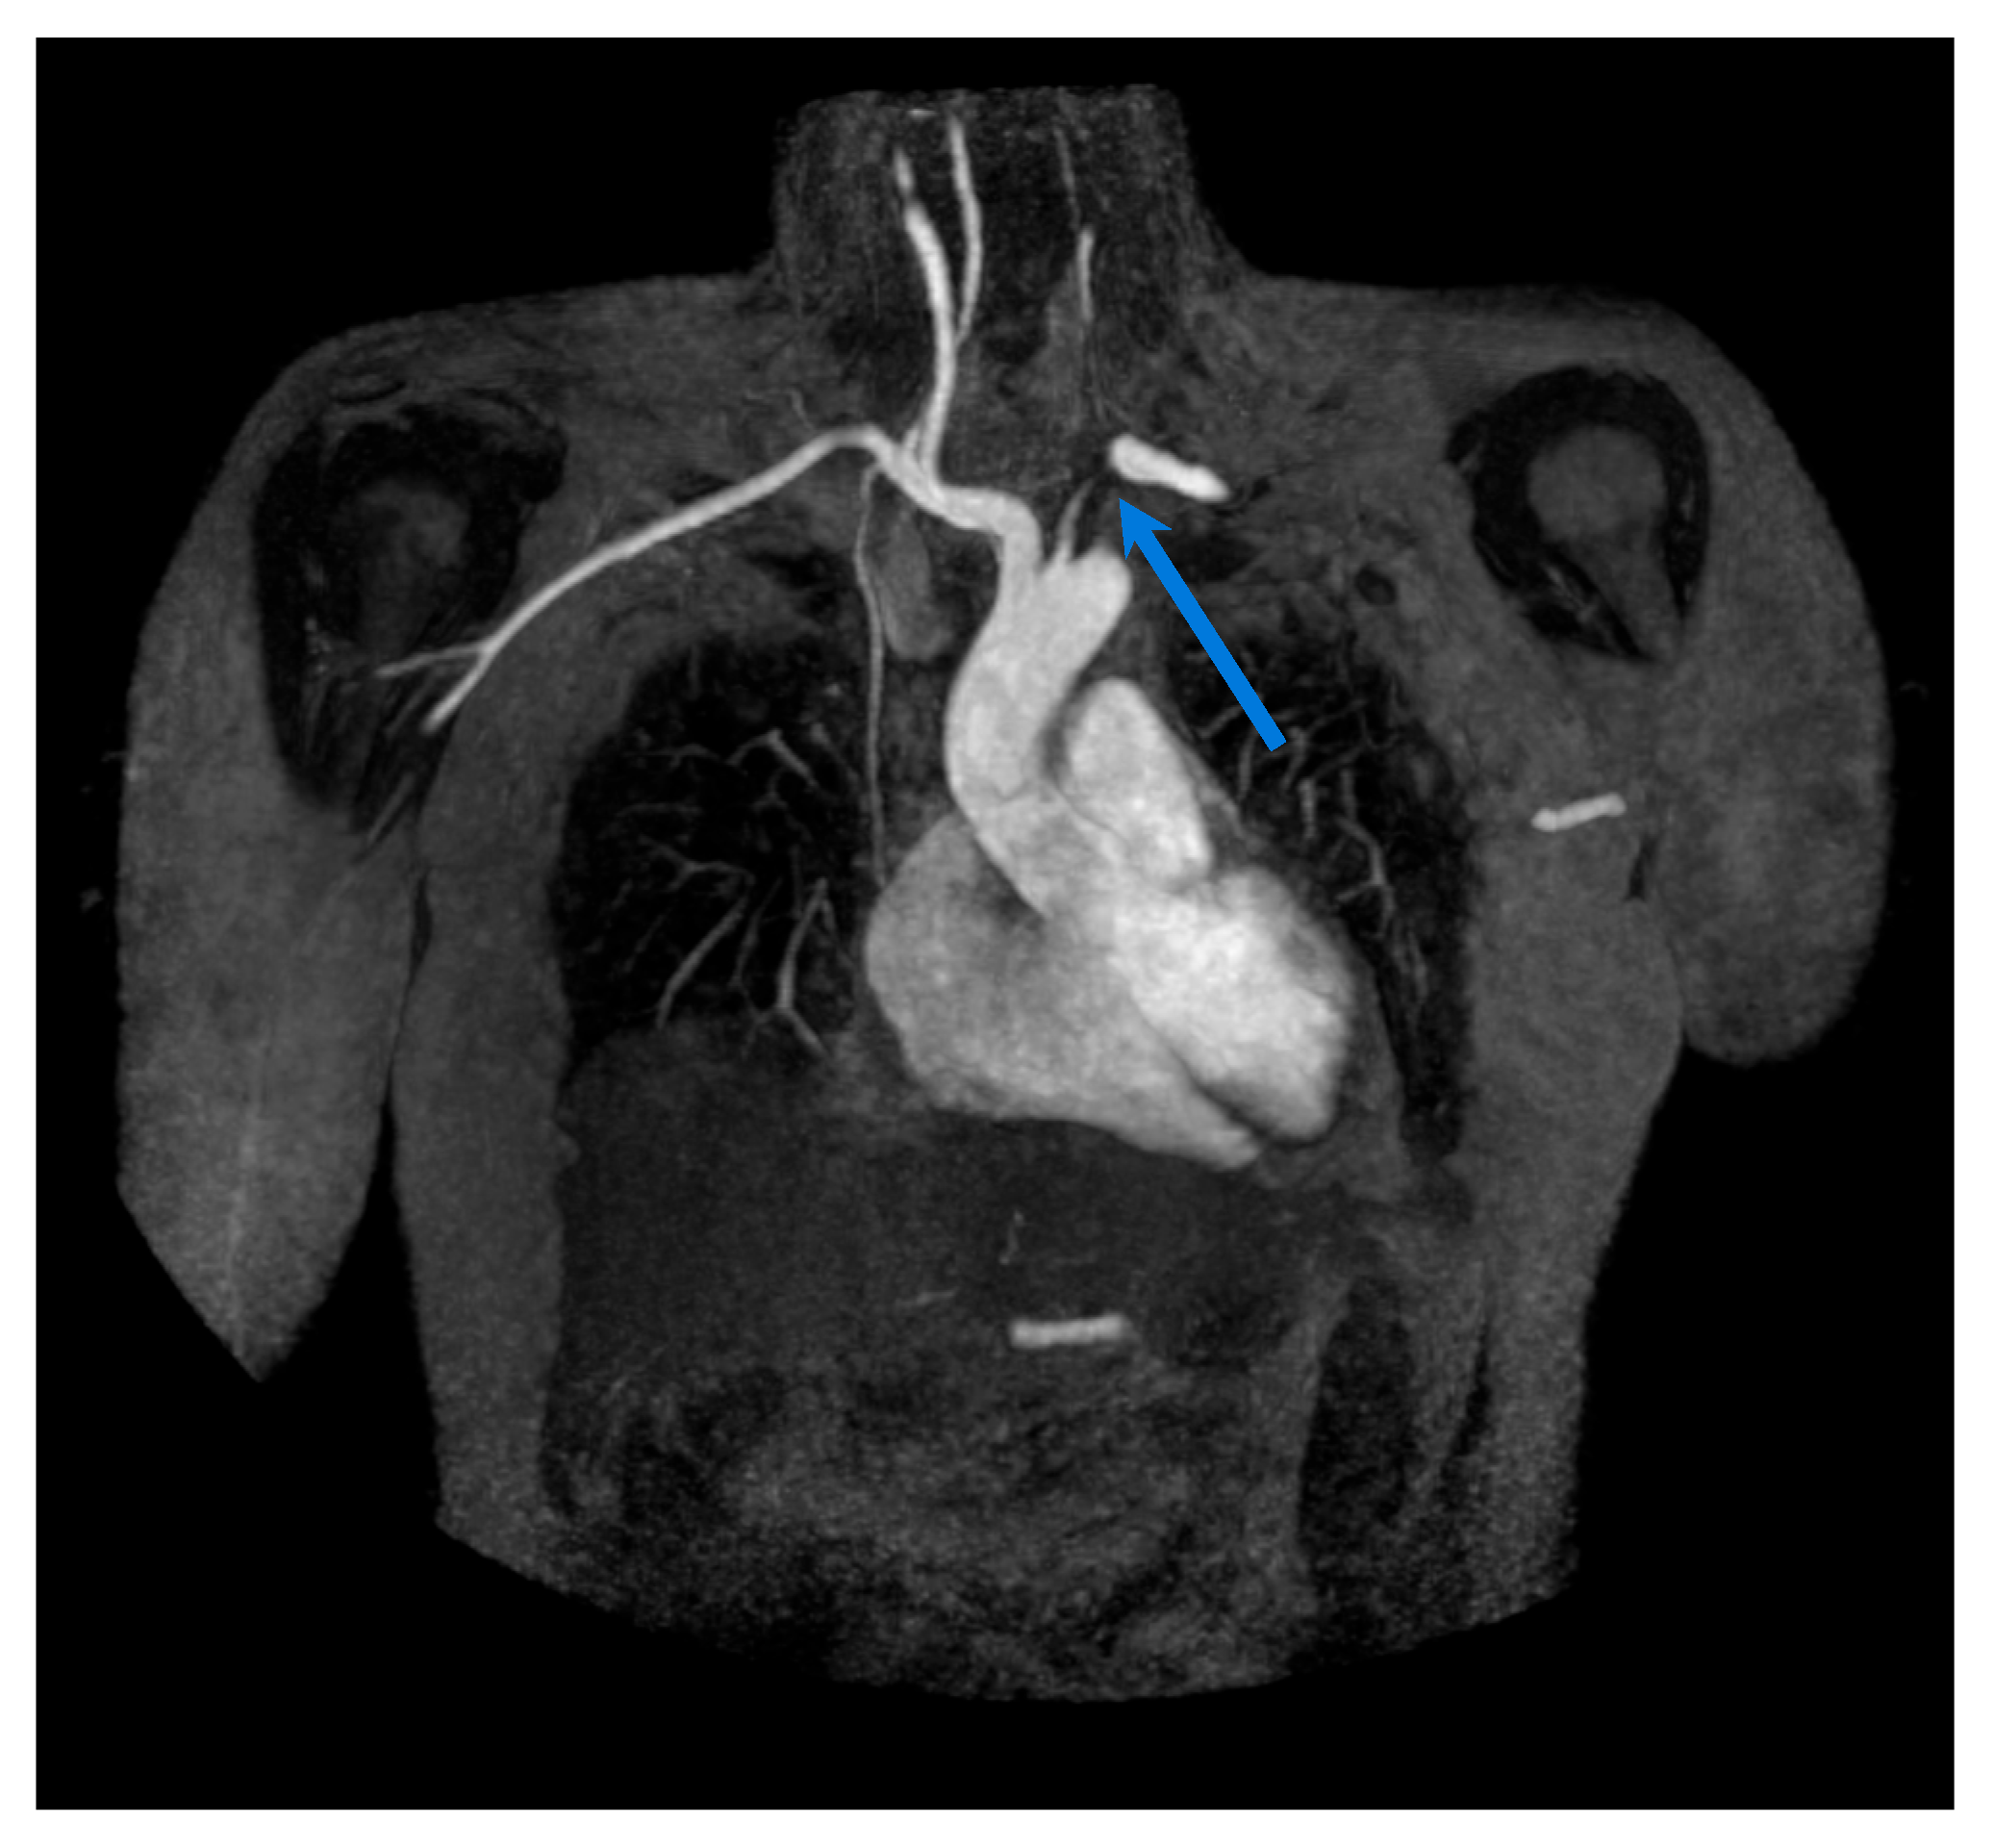

3. Magnetic Resonance Imaging

3.2. Takayasu Arteritis